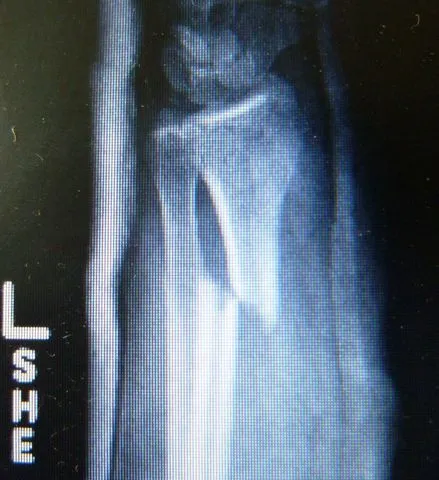

The break was clean. The orthopedic resident arrived when Alison was in X-ray. She was from Zimbabwe, and had gone to medical school 30 km outside Moscow, so she was fluent in English, Russian, Swahili, and her local tribal language. She seemed very sure of herself and she inspired confidence. She indicated that Alison would need closed reduction and a splint. It would hurt, but she could administer IV Valium.

Back in Tampa, I ordered films of Alison's arm for presentation to her orthopedic surgeon.

Alignment is not perfect, but I was told that closed reductions involve a bit of luck, and no ground has been lost because healing does not commence for a few weeks. After a curbside conference, he indicated that the best plan for optimal alignment and minimal cast time would be a plate and screws, usually not palpable or visible from the outside after healing.